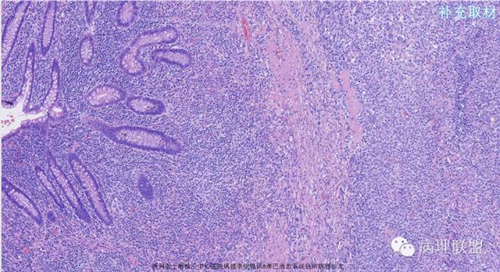

M,79岁,右半结肠粘膜下肿块。大小:6.5*6*6cm球形肿块,切面灰白质硬,界清。第一次取材。